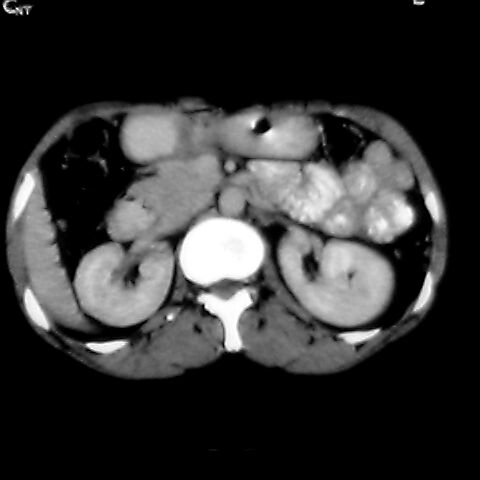

女 48岁 食道癌术前体检发现脾占位。

转移瘤不可能单发,考虑脾血管瘤。

多考虑不典型血管瘤.